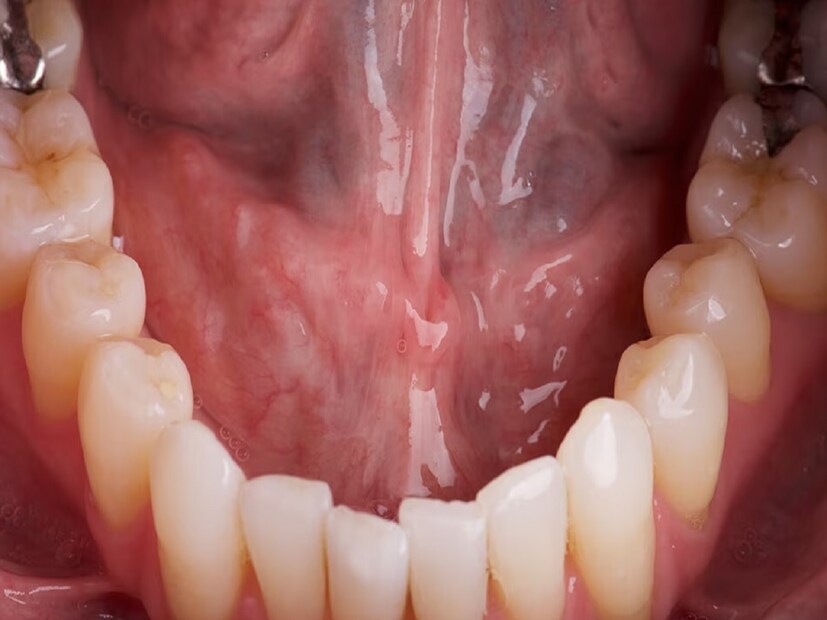

মুখের ক্যানসার আক্রান্তের সংখ্যা দিনে দিনে বাড়ছে। বিশেষ করে স্কোয়ামাস সেল কারসিনোমায় প্রচুর মানুষ আক্রান্ত হচ্ছে। কেন এই সমস্যা, কীভাবে প্রাথমিক অবস্থায় এই থেকে রক্ষা পাওয়া যেতে পারে। এই রোগ মুখগহ্বরে সবচেয়ে বেশি হয়। ইদানীং মুখের ক্যানসারের হার ভয়াবহ আকার ধারণ করছে, মৃত্যুর হারও বাড়ছে। এর অন্যতম কারণ অসচেতনতা।

এই বিষয়ে চিকিৎসক অর্ক ধারার পরামর্শ, জীবনযাত্রার মানের পরিবর্তন ক্যানসার রোগীর সংখ্যা বাড়াচ্ছে। সংখ্যার দিক থেকে আমাদের দেশে নারীদের জরায়ু ও স্তন ক্যানসার এবং পুরুষদের ফুসফুস ক্যানসারের পরই মুখগহ্বরের ক্যানসারের রোগী বেশি দেখা যায়। যাঁরা মুখের ক্যানসারে আক্রান্ত হন, তাঁদের বেশির ভাগের বয়স ৪০ বছরের বেশি। নারীদের তুলনায় পুরুষেরাই এই ক্যানসারে আক্রান্ত হন বেশি।